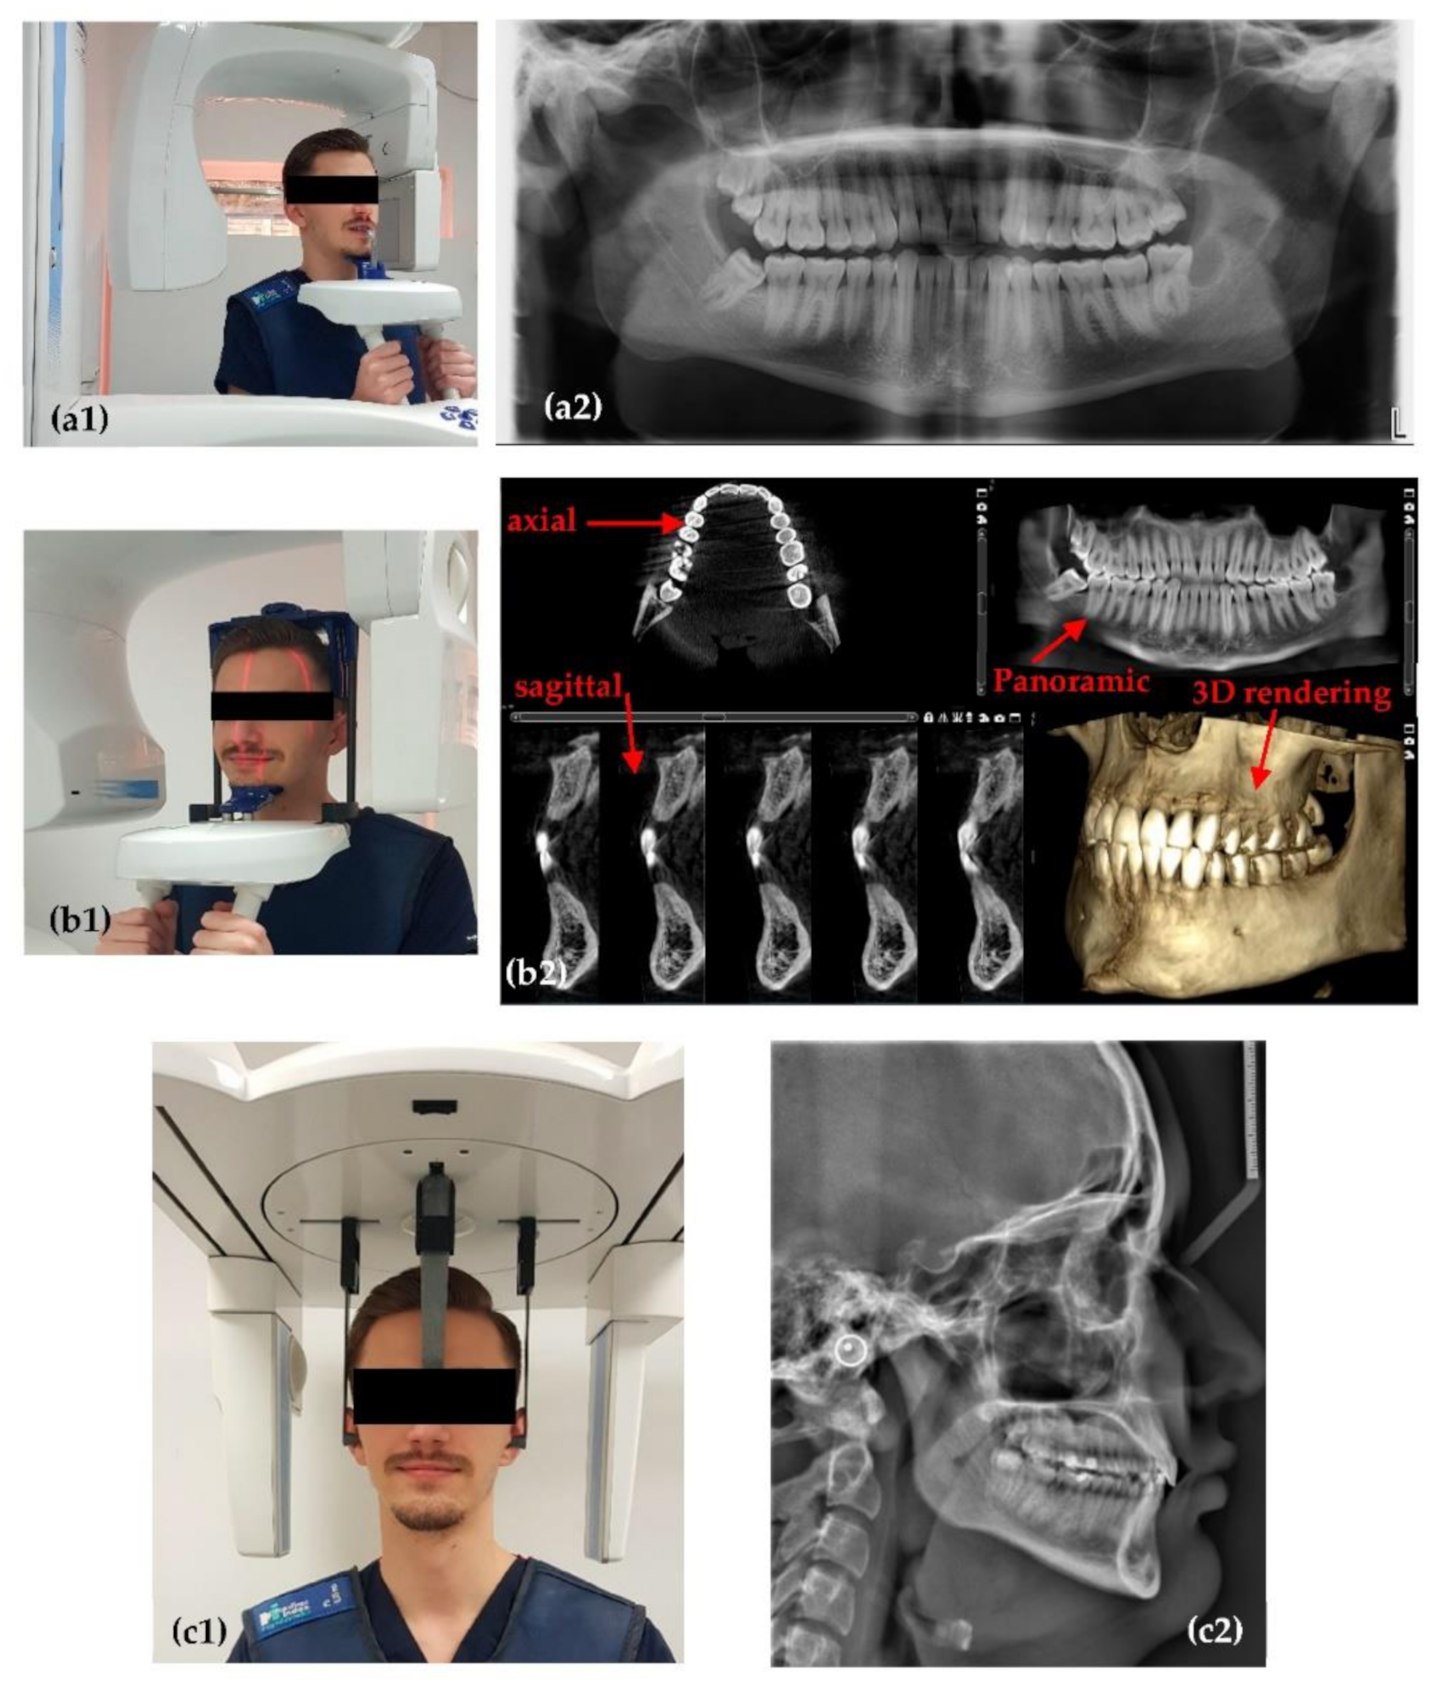

2.1. Planmeca ProMax 3D

2.2. Soredex Cranex 3D

3.1. Optimized Protocol with OCT for X-ray Imaging Calibration. Panoramic Radiography